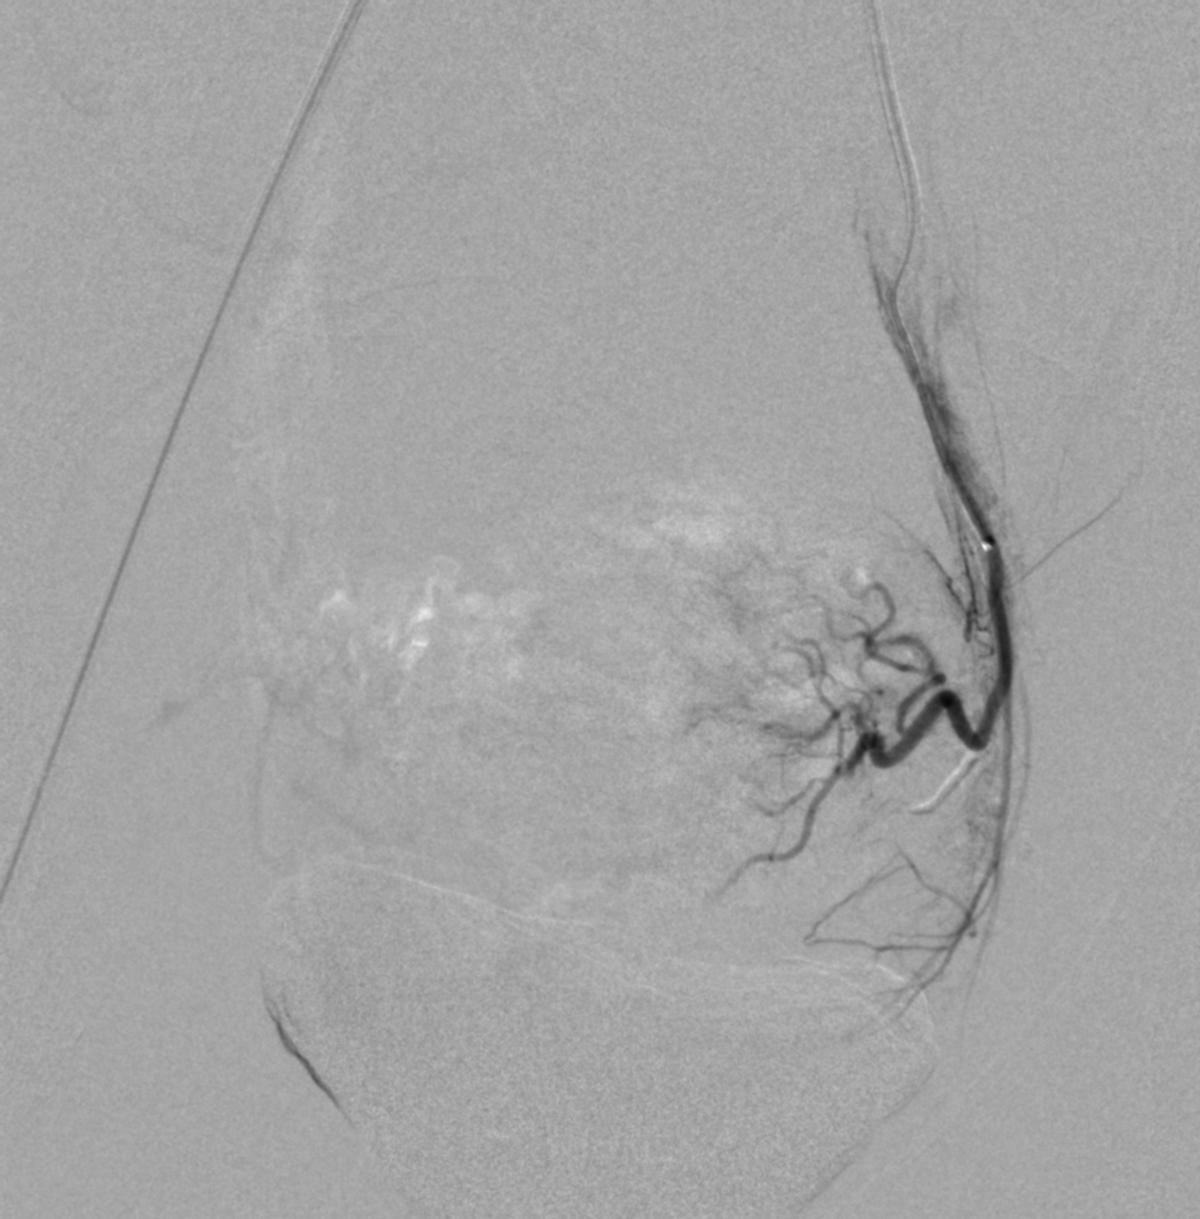

患儿完成入院前术前检查,并进行了全科的术前讨论。结合患儿体征及相关的术前检查,目*考前**虑PROS综合症。目前主要解决的是月经出血的问题,可以通过栓塞双侧子宫动脉来进行治疗。患儿全麻后,使用5F穿刺针行右股动脉穿刺,成功后置入5F血管鞘,导丝引导下置入5F Headhunter Angiopointer造影导管,在导丝引导下选入髂内动脉,进入子宫动脉,造影见左侧子宫动脉远端纤细,右侧子宫动脉螺旋增粗,微导丝引入微导管进入子宫动脉,使用聚乙烯醇颗粒栓塞剂350um-560um,栓塞微粒球(300-500um)分别行双侧子宫动脉栓塞,栓塞后造影未见子宫动脉远端分支显影。

左侧子宫动脉远端纤细

右侧子宫动脉造影